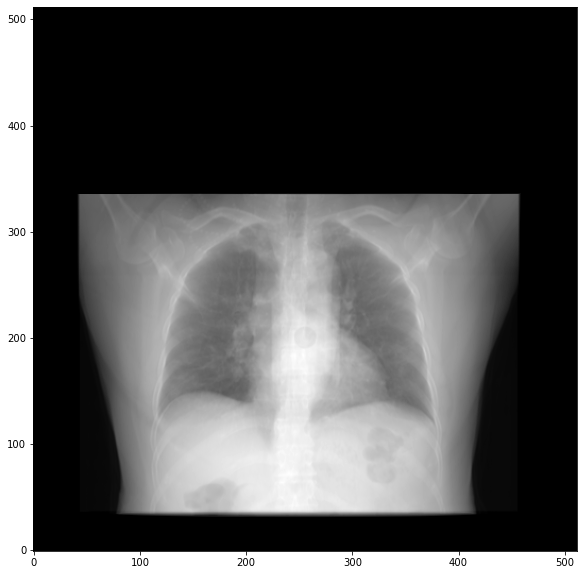

> Finally I get this DRR looks like a front-view one:

> [image: image.png]

> 1. I thought I would get a 512x512 full DRR with no backgrounds, just like

> normal x-ray, how can I fix it?